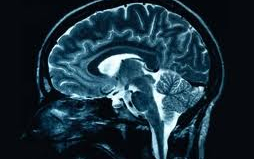

Immunterápia agydaganat ellen?

A glioblastoma az egyik legsúlyosabb agydaganat: a műtét, a sugárzás és a kemoterápia ellenére a betegség a legtöbb esetben halálos kimenetelű. Ugyanakkor állatkísérletek azt mutatják, hogy a korai stádiumban még viszonylag könnyen és jó eséllyel kezelhető - írja a Post.

Az agydaganatok kezelése különösen azért jelent nagy kihívást, mert a szabályozó T-sejtek olyan mennyiségben gyűlnek fel a daganatban, hogy elnyomják az immunrendszer ellentámadását.

Egy új stratégia és egy új gyógyszer több lépésben való használata azonban ígéretesnek tűnik Burkhard Becher, a Zürick Egyetem professzora szerint. Az eljárás során arra ösztönzik az immunrendszert, hogy még az előrehaladott állapotban lévő tumorsejteket is megölje. Ehhez az Interleukin-12 nevű anyagot használták úgy, hogy azt a tumorsejtek termelődésekor az immunsejteket úgy stimulálja, hogy azok megtámadják és elpusztítsák a daganatot.

A kísérleti vizsgálat során, miután a korai stádiumban szenvedőknél már sikereket értek el, a kutatók megvárták, amíg az állatokban a tumor nagysága már olyan méreteket ölt, amikor a kezeletlen állatoknak már csak kevesebb mint három hetük lett volna hátra az életükből.

Tehát akkor kezdték el a kezelést, amikor már túl késő volt. Ekkor az agyi tumorba bio gyógyszeripari Interleukin-12-t fecskendeztek: bár ez kiváltott némi immunválaszt, de csupán az állatok egynegyedénél.

Sikeresebb volt viszont a kutatás, amikor a módszert bőrrákon tesztelték. Ekkor az Interleukin-12-t egy új gyógyszer intravénás verziójával kombinálták. Ez esetben a vizsgált állatok 80 százalékánál működött a beavatkozás.